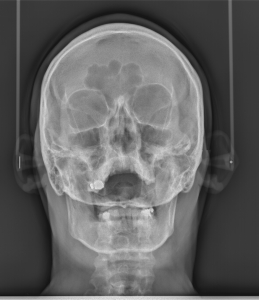

Рентгенова снимка на СИНУСИ

Рентгеновата снимка обхваща максиларните и фронтални синуси с която се диагностицират заболявания на сиунсите, както и одонтогенна патология причинена от заболявания на зъбите.